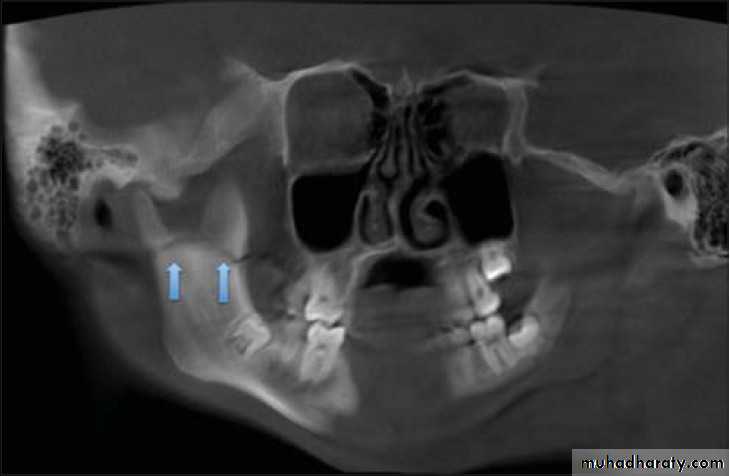

Angle Fracture:This is the most common fracture after condylar neck fracture. The angle is a weak area since it is the junction of the ramus and the body of the mandible, also the presence of an impacted mandibular third molar weakens the area. The fracture in this area may be classified as favorable and unfavorable fracture depending on the severity of posterior fragment displacement. The displacement depends on the pull direction of the masseter and / or the medial pterygoid muscles, and the direction of the fracture line vertically andhorizontally through the bone.

In practical view, if the fracture is relatively stable, itis considered a favorable fracture irrespective of the direction of the fracture line, also the presence of an erupted tooth in the posterior fragment which aid in the reduction and immobilization of such fracture regarded as favorable fracture. The signs and symptoms are ecchymosis, swelling, tenderness and bony step deformity.

2. Extra-oral radiographsI. Oblique lateral of mandible (right and left side views); to evaluate thefracture line in the body, angle and condylar neck fracture.II. Postero-anterior view of mandible; to evaluate body and angle #together with the type of displacement.III. Panoramic tomogram, or orthopantomogram (OPT): the best single overallview of the mandible, including excellent view of the condyles.tic resonance imaging); which gives very accurate details.

IV. Reverse Towne's view (elongated PA); to demonstrate fractures of thecondylar neck.v. Temporomandibular joint views (in open and close mouth); todemonstrate the presence of TM dislocation (Transcranial,Transpharyngeal, Arthrography, and Arthroscopy)VI. CT scan (computerized tomography scanning); to evaluate intracapsular fracture of the condylar head.VII. MRI